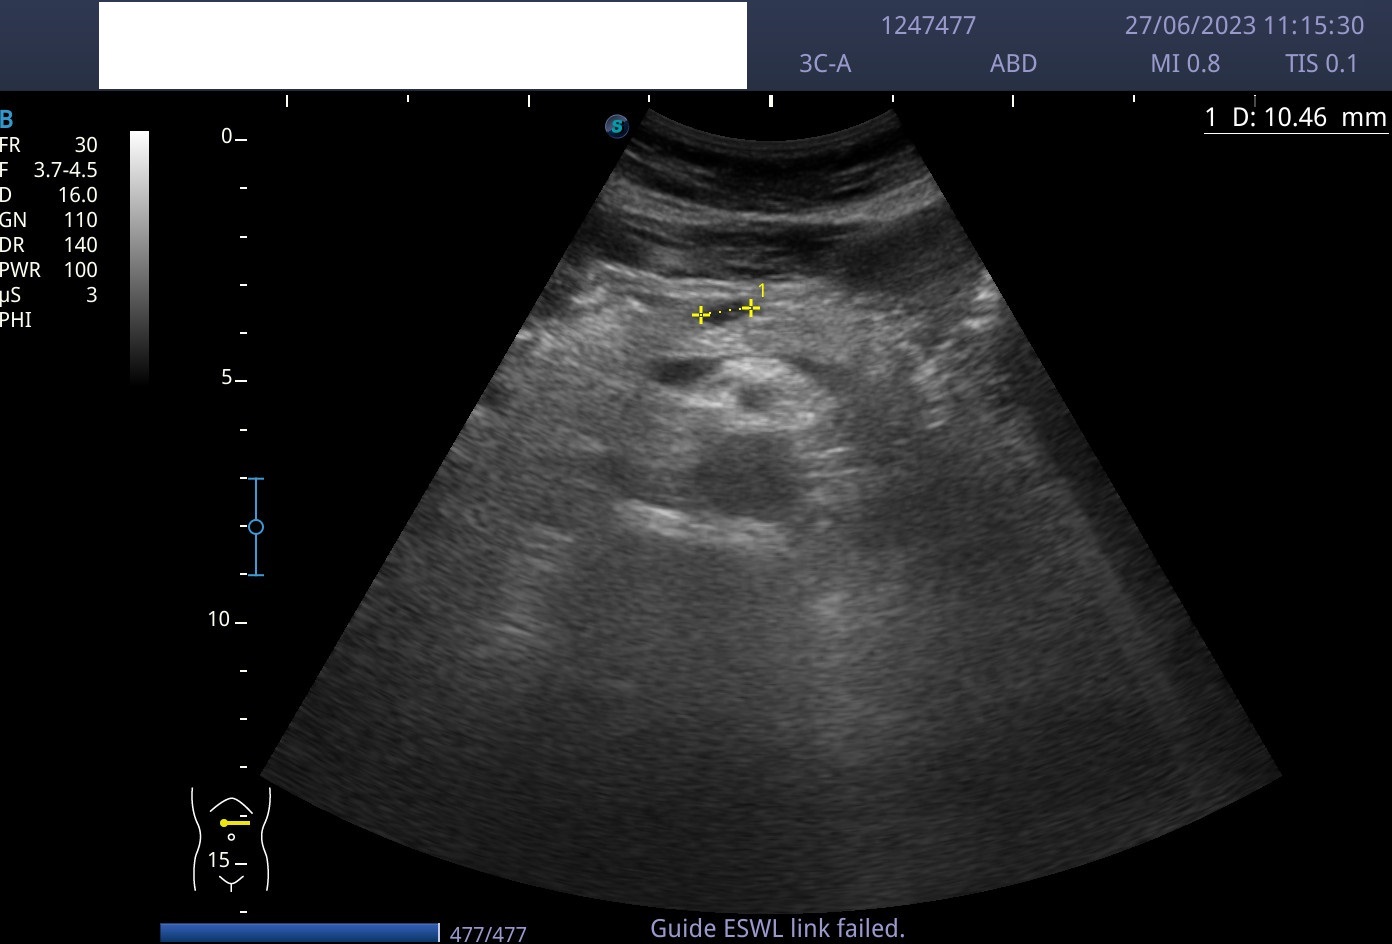

Hallazgos ecográficos

Lesión anecoica bien circunscrita de paredes lisas, con refuerzo posterior, de 1 cm de longitud, localizada en cuerpo pancreático, sin captación Doppler.

Ecografía abdominal reglada en Hospital de referencia con misma sospecha clínica que la realizada en Atención Pirmaria.